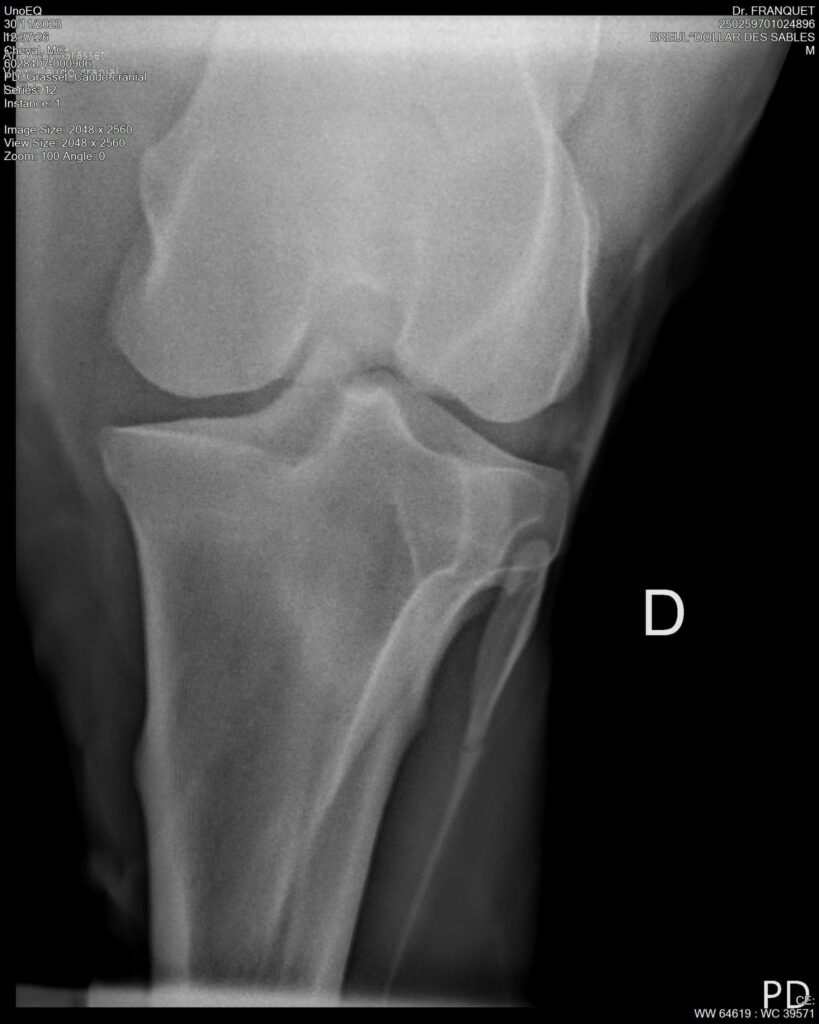

DOLLAR DES SABLES, Selle Français, hongre, 12 ans par DOLLAR DE MURIER x ABKE (ACORADO). Classé 135 avec professionnel à fait 125 avec amateur, récemment classé sur amateur 1GP 120. Très beau modèle ! Gentil cheval, respectueux avec des moyens et du sang. Transport OK, maréchalerie OK, santé RAS, Bilan clichés radios OK.

RADIOS